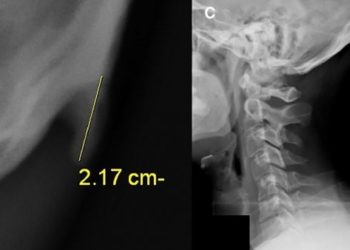

La protuberancia, que puede superar los 20 milímetros, aparece de forma "significativamente más probable" entre las personas jóvenes, según un ...